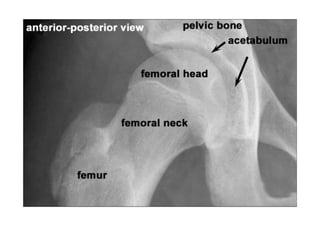

Referência: http://www.accessexcellence.org/RC/VL/

figura